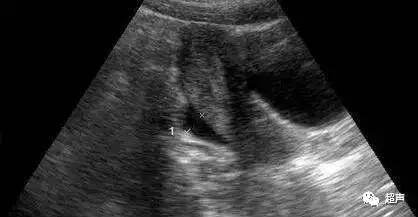

超声显示子宫和两侧附件声像图正常,盆腔积液深度<20mm,其原因可有以下几个方面:

②排卵期,即卵泡破裂,子宫直肠陷窝或卵巢周围少量积液无回声区,可能系卵泡破裂后卵泡液的积储所致,亦有认为系腹膜对排卵的反应;